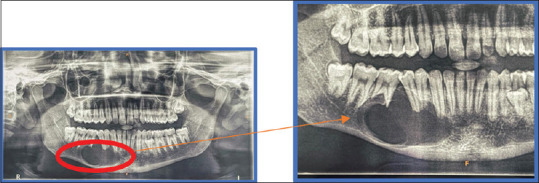

Mandibular ameloblastoma are rare, noncancerous tumors which originate from odontogenic epithelium. Ameloblastoma, commonly occurring in the mandible, disturbs its balance and symmetry. Surgical treatment of ameloblastoma though gets rid a patient of the tumour, but it may also result in compromised esthetics and function. The present case report focuses on the implant-supported rehabilitation of the mandibular region treated with surgical enucleation of the tumour.